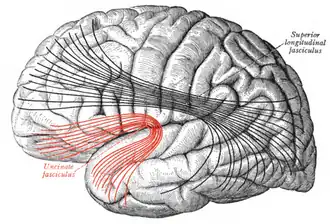

Lateral surface of left cerebral hemisphere. Some of the major association tracts are depicted. Uncinate fasciculus is at lower left, in red. | |

Diagram showing principal systems of association fibers in the cerebrum. (Uncinate fasc. visible at lower left, in red.)

Diagram showing principal systems of association fibers in the cerebrum. (Uncinate fasc. visible at lower left, in red.) -